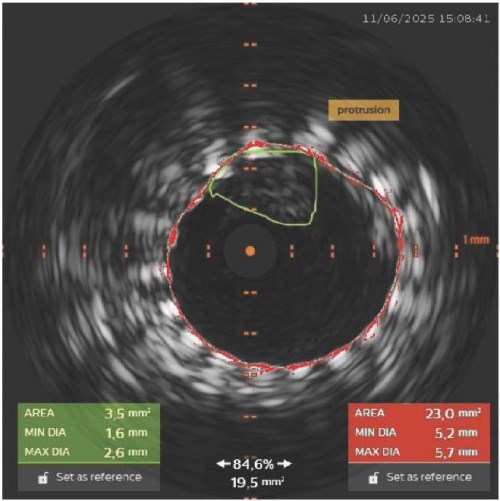

• Применение внутрисосудистого ультразвукового исследования (ВСУЗИ) позволило своевременно диагностировать протрузию бляшки через стент, не видимую ангиографически.

• Интраоперационный контроль с помощью ВСУЗИ обеспечил индивидуальный выбор тактики и предотвращение инсульта.

• ВСУЗИ подтвердило устранение протрузии и аде­кватное прилегание стента после серии бал­лонных дилатаций.

• Представленный случай подчёркивает стратегическое значение ВСУЗИ в безопасном проведении каротидного стентирования.

Каротидная ангиопластика со стентированием (КАС) является альтернативой хирургическому лечению у пациентов с высоким операционным риском при каротидной эндарэктомии. Согласно результатам крупного рандомизированного контролируемого исследования CREST (Carotid Revascularization Endarterectomy versus Stenting), существенных различий в частоте инсультов, инфарктов и смертей в группе КАС и каротидной эндарэктомии в отдаленном периоде нет. Однако значительное количество осложнений в группе КАС связано именно с перипроцедуральным периодом. Безопасность КАС напрямую зависит от технической успешности вмешательства и минимизации риска церебральной эмболии. Несмотря на использование эмболопротективной защиты в 100% случаев, профилактика инсульта остается актуальной проблемой. На примере клинического случая продемонстрировано влияние интраоперационного внутрисосудистого ультразвукового исследования (ВСУЗИ) на тактику вмешательства и профилактику осложнений при КАС, а также предложен алгоритм действий при интраоперационной протрузии бляшки.

Представленный клинический случай подтверждает, что ВСУЗИ является не просто диагностическим, а стратегическим инструментом, позволяющим индивидуализировать лечение на всех этапах КАС. Рутинное применение ВСУЗИ для оценки морфологии бляшки, интраоперационного контроля и управления осложнениями способно существенно повысить безопасность процедуры. Предложен алгоритм ведения пациентов с протрузией бляшки.